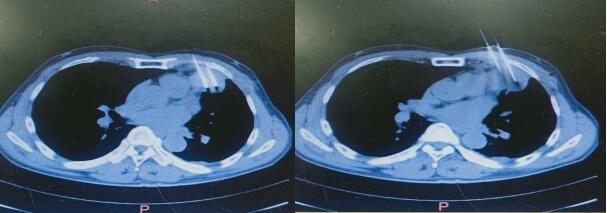

↑ 术后1个月恢复情况

患者陶某,2020年12月13日因胸痛来我院就诊,门诊给予胸部CT检查显示左肺上叶肿瘤并左肺内转移,之后住入血液内科,入院完善检查后行CT引导下肺肿瘤穿刺活检,术后病理示:左肺鳞癌,刘金峰主任根据患者情况给予综合评估,考虑患者胸痛明显,结合最新治疗指南后于2020年12月25日行左肺癌碘125粒子置入术,手术顺利,术后恢复好。术后10余天胸痛就明显好转。为进一步巩固治疗,之后再次给予全身化疗4周期。患者目前胸痛消失,胸部肿瘤较前体积明显缩小。